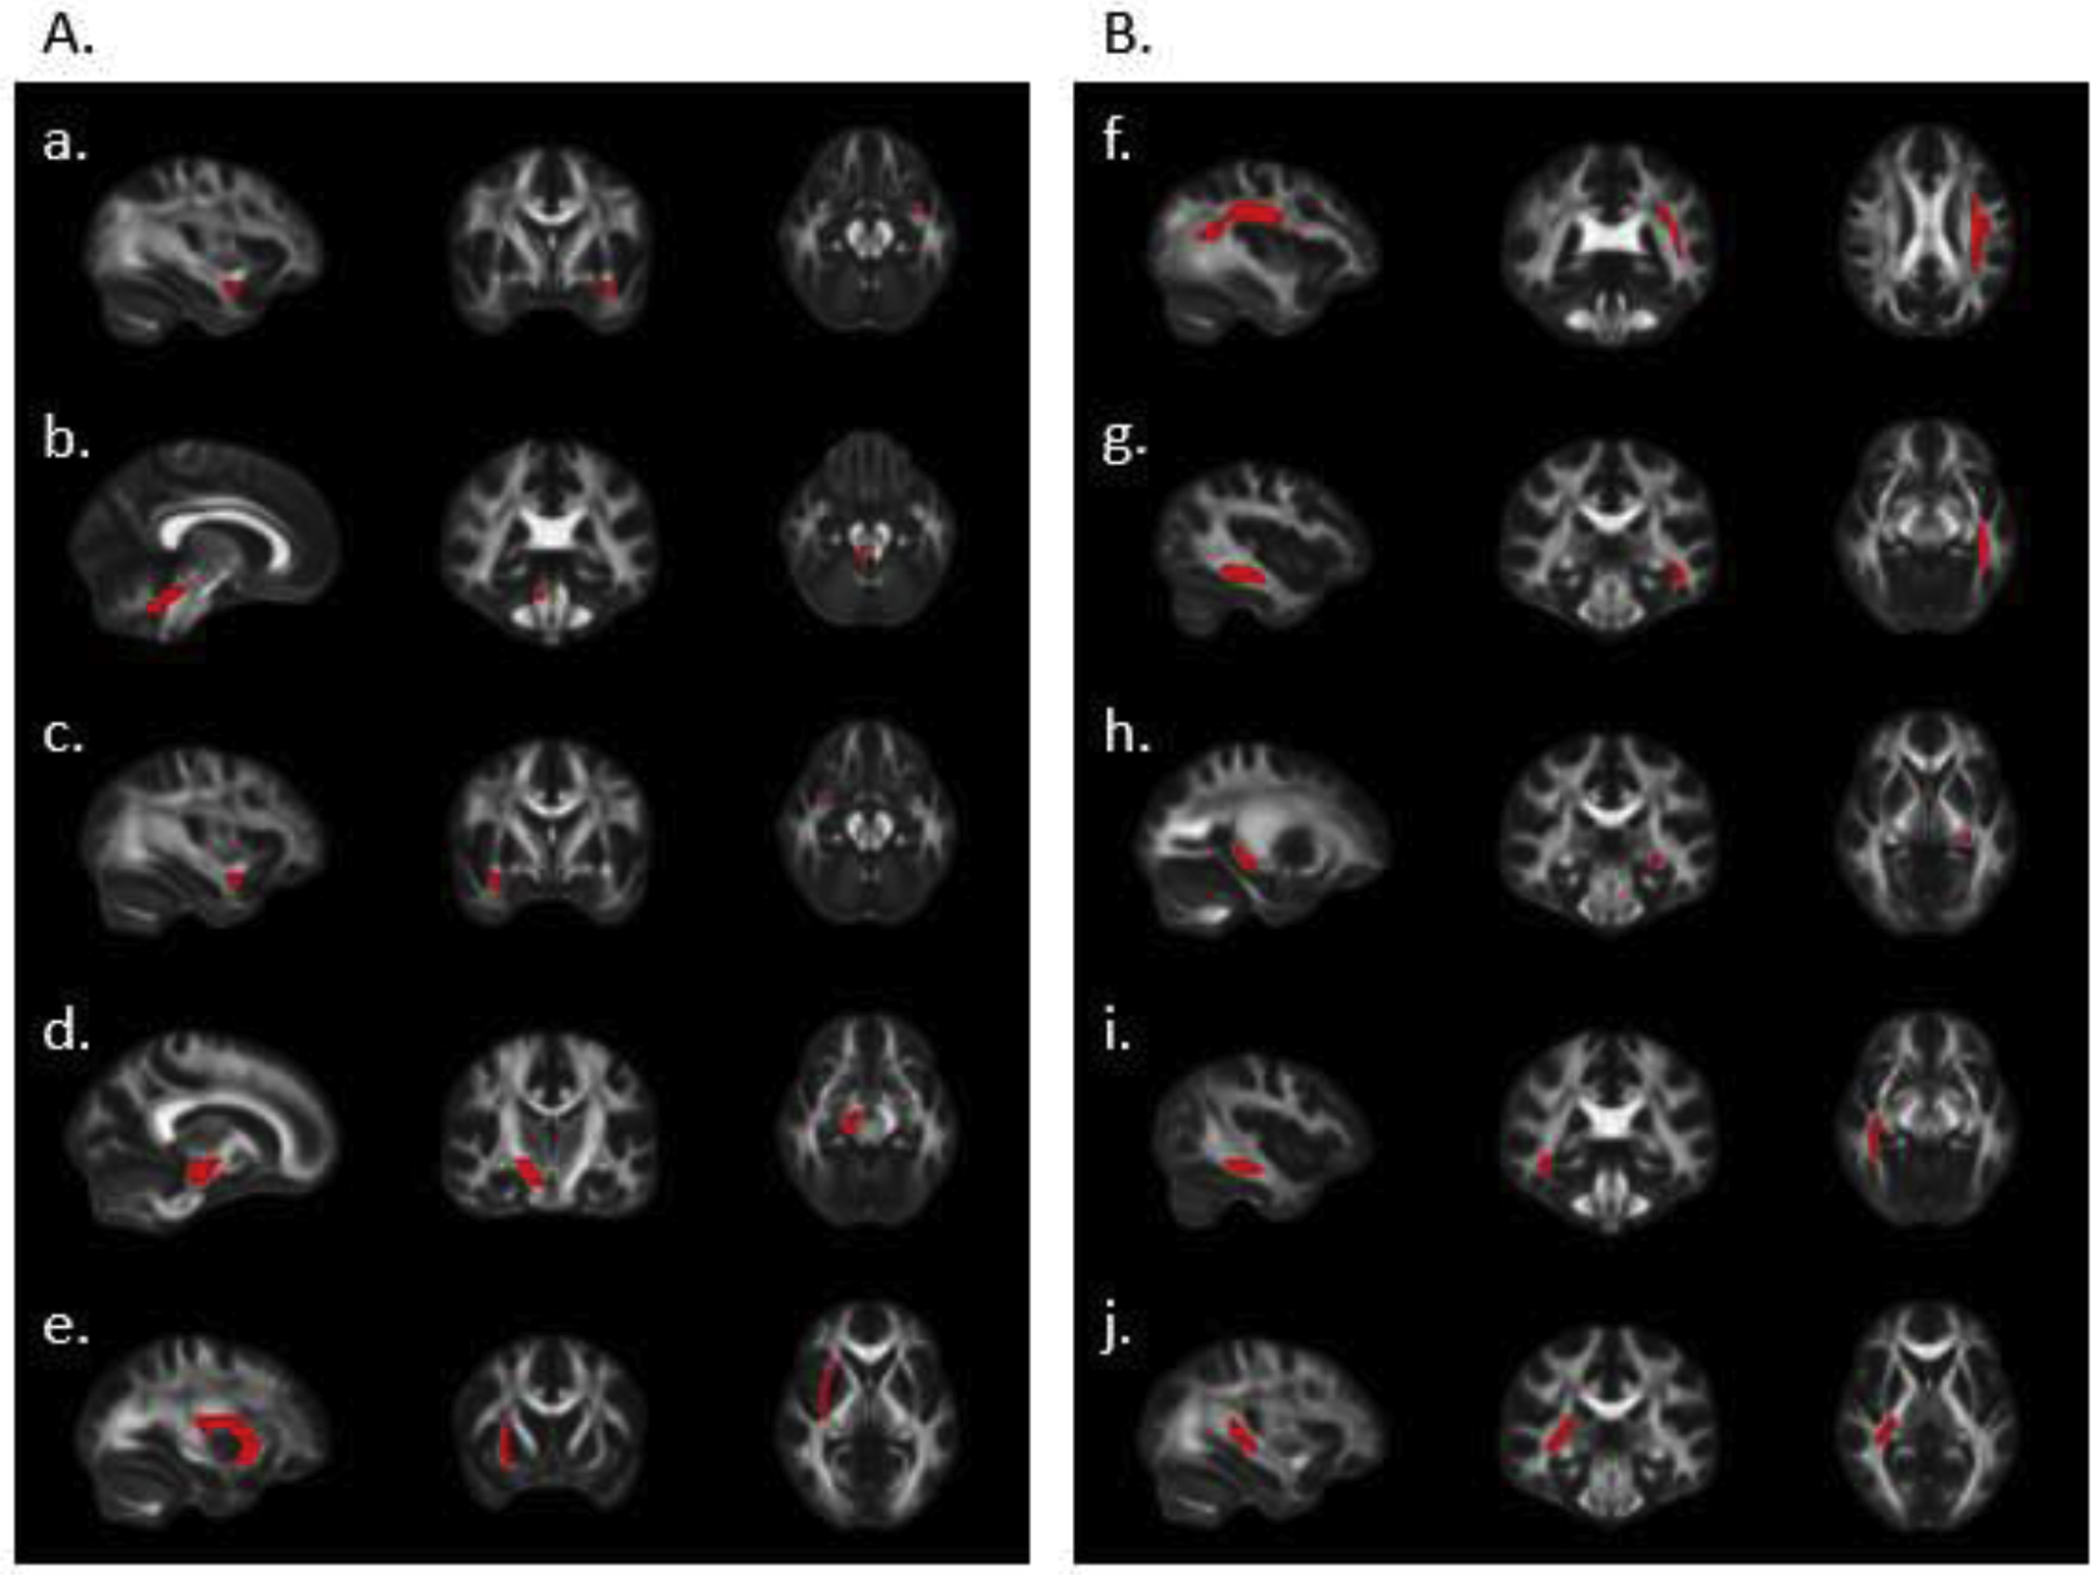

Description:Welding fume exposure has been associated with structural brain changes and a wide variety of clinical and sub-clinical outcomes including cognitive, behavioral and motor abnormalities. Respirator use has been shown to decrease exposure to welding fumes; however, the associations between respirator use and health outcomes, particularly neurologic health, have been understudied. In this preliminary study, we used diffusion tensor imaging (DTI) to investigate the effectiveness of respirator use in protecting workers' white matter (WM) from the harmful effects related to welding fume exposure. Fractional anisotropy (FA), a common DTI measurement of water diffusion properties, was used as a marker of WM microstructure integrity. We hypothesized that FA in brain regions involved in motor and neurocognitive functions would differ between welders reporting respirator use compared to those not using a respirator. We enrolled a pilot cohort of 19 welders from labor unions in the New York City area. All welders completed questionnaires to assess welding history and occupational health. All completed a DTI acquisition on a 3 T Siemens scanner. Partial least squares discriminant analysis (PLS-DA), a bioinformatic analytical strategy, was used to model the divergence of WM microstructures in 48 regions defined by the ICBM-DTI-81 atlas between respirator users compared to non-users. This yielded an effective discrimination of respirator users from non-users, with the uncinate fasciculus, the cerebellar peduncle and the superior longitudinal fasciculus contributing most to the discrimination of these groups. These white matter tracts are involved in widespread motor and cognitive functions. To our knowledge, this study is the first to suggest a protective effect of respirator on WM microstructure, indicating that the lack of respirator may present unsafe working conditions for welders. These preliminary findings may inform a larger, longitudinal intervention study that would be more appropriate to investigate the potential protective effect of respirator usage on brain white matter in welders.